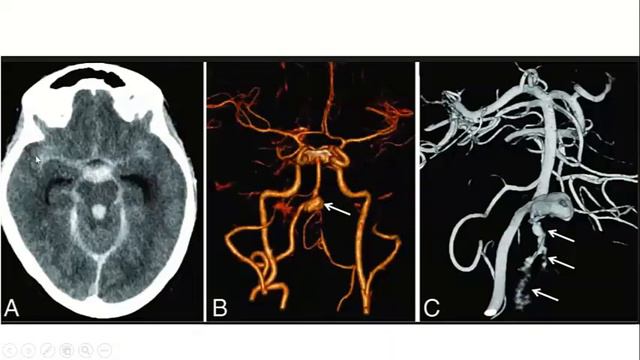

Бурденко аневризма

Бурденко аневризма 107 фото